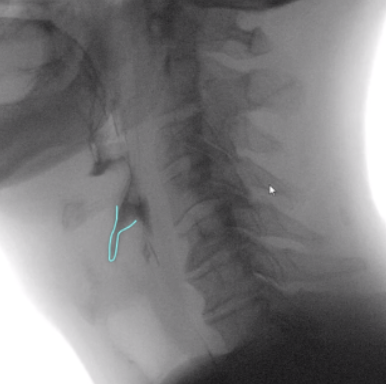

Laryngeal Vestibule Integrity

Quick Takeaways

The presence or absence of laryngeal vestibule closure (LVC) can be captured during MBSS analysis. Although this is a dichotomous variable, not a quantitative measure, this physiologic parameter is detailed in this document, given its established importance in airway protection and its contribution to comprehensive swallow analysis when interpreted in conjunction with quantitative measures.

This data point is collected with the ASPEKT-C Method.

Steps for Completion

Using frame-by-frame analysis, review the clip to assess the integrity of the laryngeal vestibule closure.

Determine - was LVC complete or incomplete?

Note: Normative data indicate that complete laryngeal vestibule closure is typical, whereas incomplete closure is atypical.

Example: Use of freehand tool in TIMS MVP demonstrating incomplete laryngeal vestibule closure.